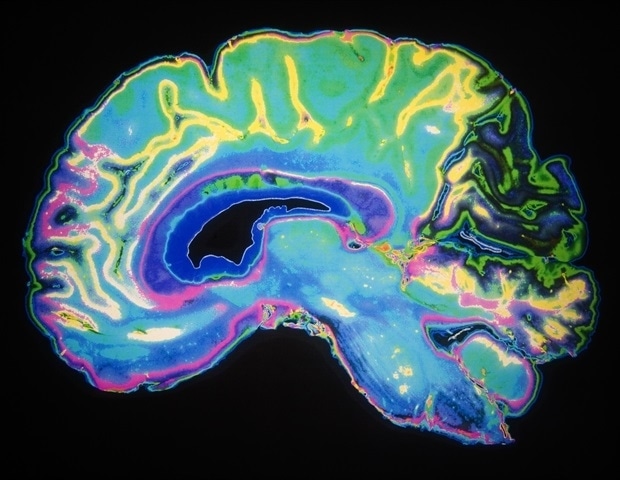

Ολιστική προσέγγιση στην υγεία του εγκεφάλου και της καρδιάς

Μια νέα κατευθυντήρια γραμμή για την υγεία του εγκεφάλου και της καρδιάς υιοθετεί μια ολιστική προσέγγιση, ενσωματώνοντας στοιχεία από τη νευρολογία και την ψυχική υγεία με οδηγίες για την καρδιοαγγειακή νόσο. Αυτό είναι ιδιαίτερα σημαντικό, καθώς πολλές παθήσεις του εγκεφάλου και της καρδιάς παρουσιάζουν αλληλεπικαλύψεις και κοινά παράγοντα κινδύνου. Η κατευθυντήρια γραμμή δημοσιεύθηκε στο CMAJ (Canadian Medical Association Journal).